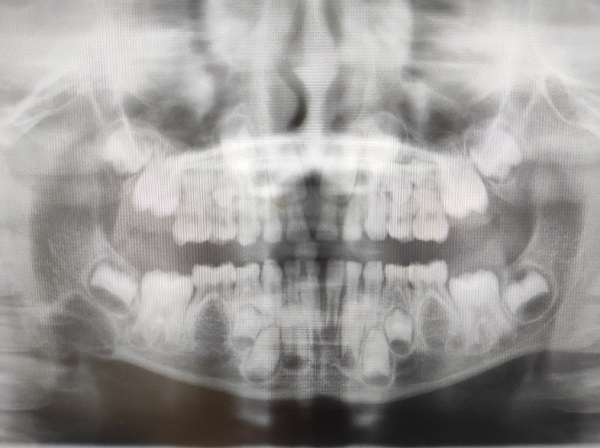

Se solicita radiografía y ortopantomografía, evidenciándose lesión redondeada radiolúcida de aproximadamente 12 x 5 mm que hace sospechar posible ameloblastoma (Figura 1).

Figura 1. Lesión redondeada radiolúcida de aproximadamente 12 x 5 mm